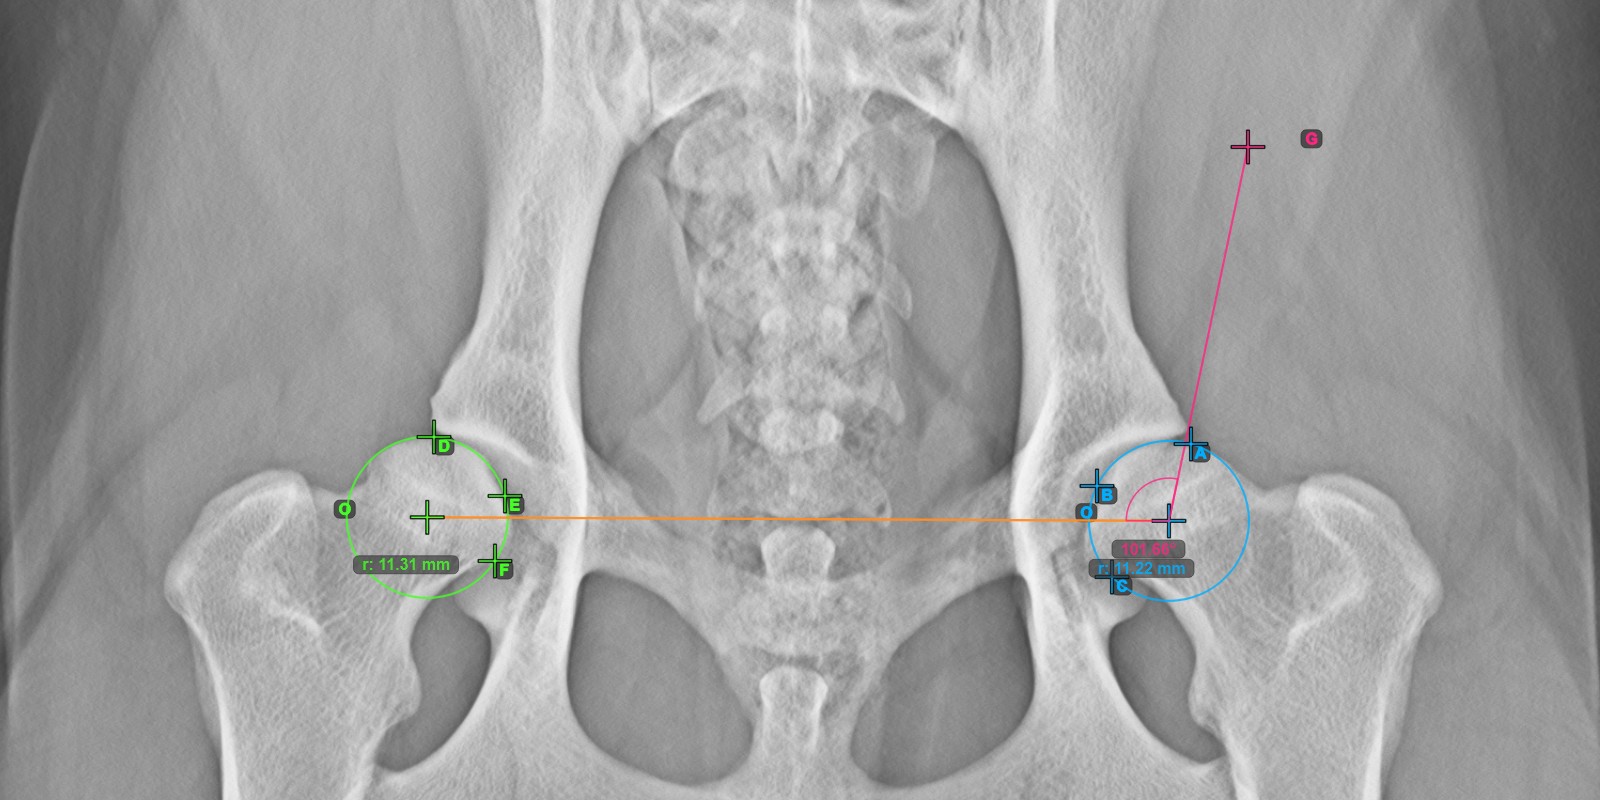

Das untenstehende Bild zeigt die typische Platzierung der drei Punkte auf der Gelenkfläche des linken Caput Femoris.

Markieren Sie die drei Punkte auf der Gelenkfläche des linken Caput Femoris (außerhalb der Fovea Capitilis). Unabhängig von der Reihenfolge stellen Sie sicher, dass der kranialste Punkt, der kaudalste Punkt und der Mittelpunkt des Femurkopfes markiert werden. Basierend auf den drei platzierten Punkten wird automatisch ein Kreis erstellt.